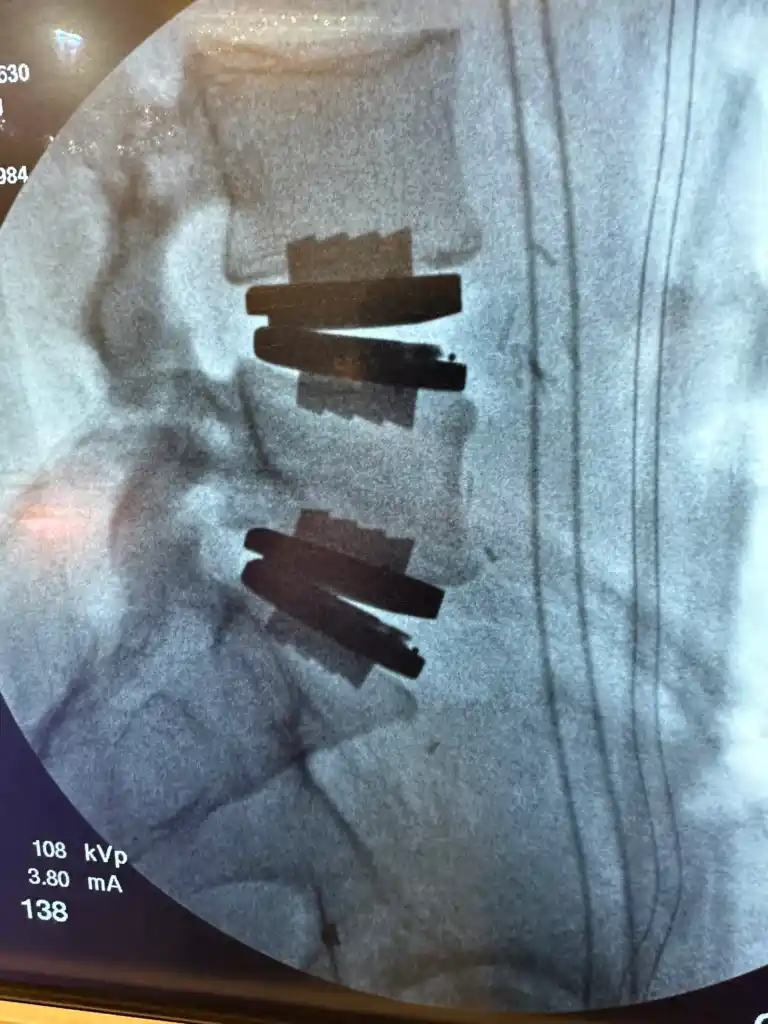

Lumbar disc replacement

Lumbar disc replacement